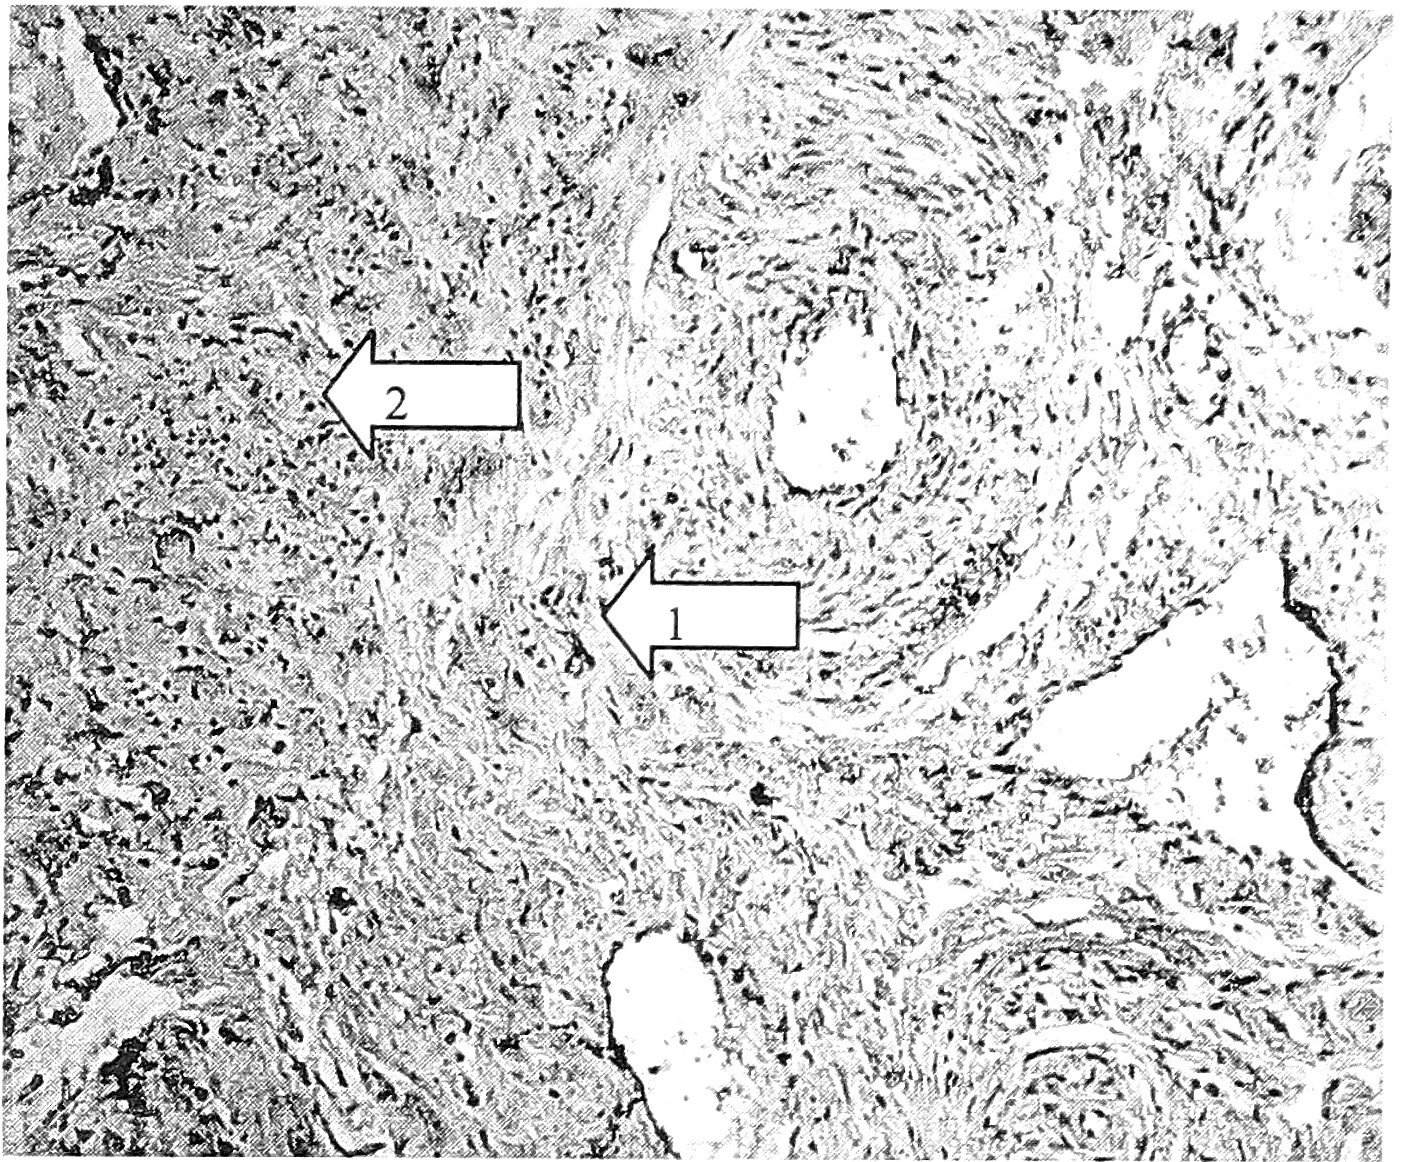

прессии бета-трансформирующего фактора роста в клетках стромы и экстрацеллюлярном матриксе, в контрольной группе его экспрессия обнаруживается лишь в эпителии слизистой. Экспрессия фактора роста фибробластов в основной группе наблюдается, в отличие от контрольной, не только в строме, но и в экстрацеллюлярном матриксе (рис. 4, 5).Существенных возрастных отличий изученных показателей не обнаружено (табл. 2).

Рис. 4. ЭШМ I степени, ДСТ легкой степени (пациентка 34 лет). Выраженная экспрессия бета-трансформирующего фактора роста в экстрацеллюлярном матриксе (1) и в клетках стромы (2). Ув. 400.

Рис. 5. ЭШМ I степени, ДСТ умеренной степени (пациентка 39 лет). Экспрессия фактора роста фибробластов в клетках стромы (1) и экстрацеллюлярном матриксе (2). Ув. 400.